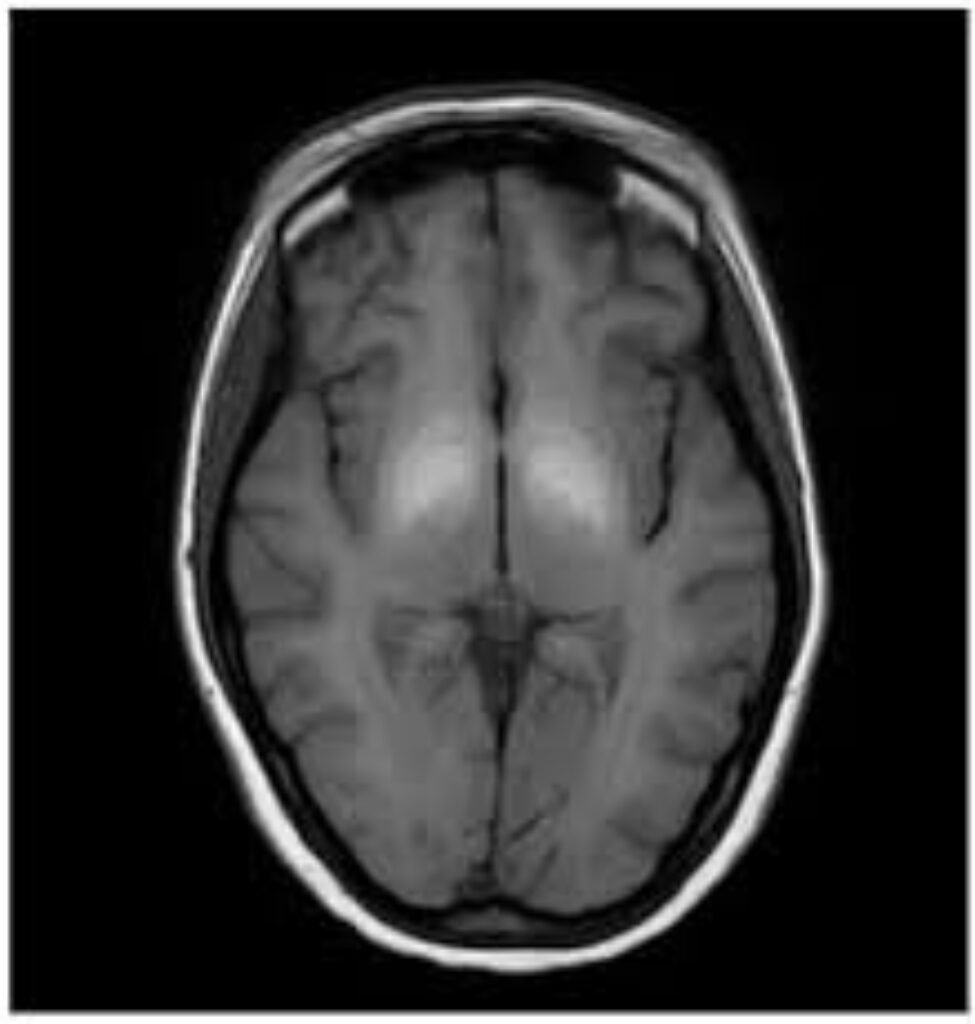

The truth is, an MRI can reveal critical details about your health that no other scan can match. Unlike X-rays or CT scans, which mainly show bones and dense structures, an MRI captures high-resolution images of soft tissues, including the brain, nerves, muscles, organs, joints, and blood vessels.

- ✔ Brain changes linked to dizziness, seizures, headaches, and memory issues